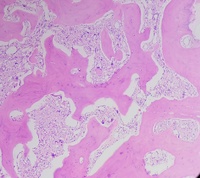

Primary myelofibrosis (PMF) with osteosclerotic progression 1

Author: Dr.Vikram Prabhakar

Category: Myeloid Neoplasms and acute leukemia (WHO 2016) > Myeloproliferative Neoplasms (MPN) > Primary Myelofibrosis (PMF)

Primary myelofibrosis (PMF) with osteosclerotic progression. Patient presented with pancytopenia and massive splenomegaly